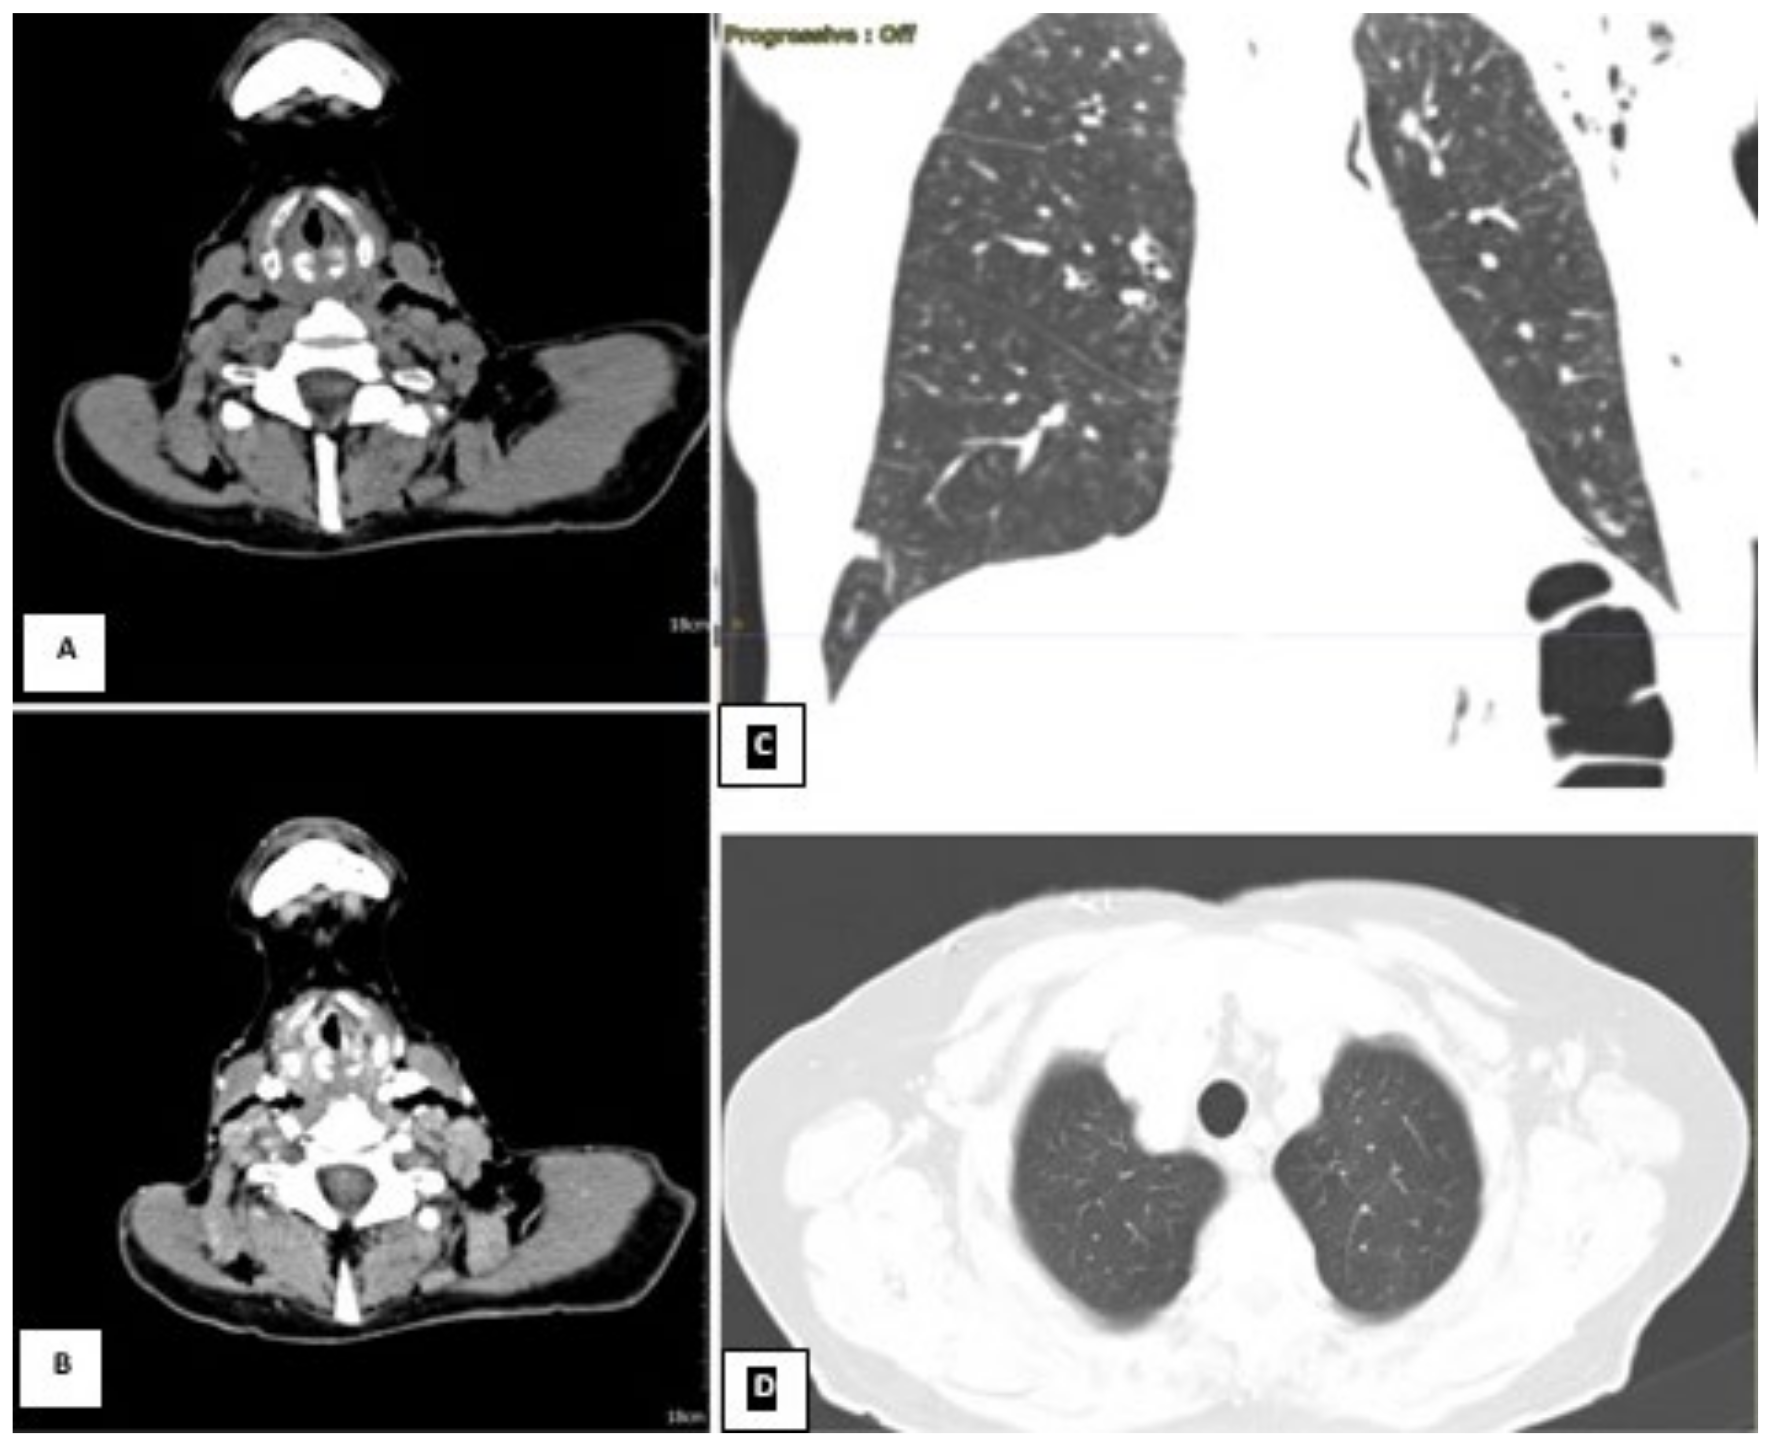

Figure 4.

CT scan on the left. The neck scan revealed the presence of small submucosal bilateral glottic masses, associated with increased cervical lymph node volume, without subglottic and extra laryngeal extensions. (A) Axial section basal CT scan on the left. (B) Axial contrast-enhanced CT on the right. Lung window showing a small scar at the level of the right lower lobe from previous pneumonia reported by the patient; (C) coronal and (D) axial lung window). Due to the worsening conditions, the patient was mechanically ventilated because of acute respiratory failure. Despite the therapy and mechanical ventilation, the pulmonary functions deteriorated progressively, resulting in the patient’s death. The patient was not diabetic, hypertensive, or cardiopathic and was not a smoker. By anamnestic clinical history, we discovered that two years before this event (October 2019), the subject presented mild hoarseness of voice. At the time, an endoscopic laryngeal examination revealed bilateral mobile vocal folds without apparent abnormalities. For further confirmation, the subject underwent a laryngeal exam under general anesthesia, which showed the absence of any macroscopic lesion, and the histopathological results of the biopsies were negative. The physicians scheduled a follow-up after three months, but unfortunately, the lockdown caused by the COVID-19 pandemic and the fear of viral infection prevented her to attend the recommended follow-up visits. The patient was COVID-19-negative throughout the whole illness (Table 1). We performed a literature analysis by searching the PubMed database for ‘laryngeal adenoid cystic carcinoma’. We did not limit the search to article types because of the rarity of the disease and the little number of papers about it. We choose only papers published in English within the past five years. The articles in the database whose full text could not be found were also excluded. The title and abstracts of the identified manuscripts were initially screened and selected by all authors independently (IF, AC, PGM, HE, RA, MF, MR, DM, AG, MdV, CB, and AM) based on their relevance to the review topic. The following set of shared chosen inclusion criteria was applied individually to the selected articles in their full-text version: primary laryngeal affection of adenoid cystic carcinoma and therapy consensus of LACC. The literature search yielded 48 papers. Subsequently, 28 studies were excluded because they did not meet the objective of our review, and 20 studies were included and discussed (Figure 5 and Table 2).